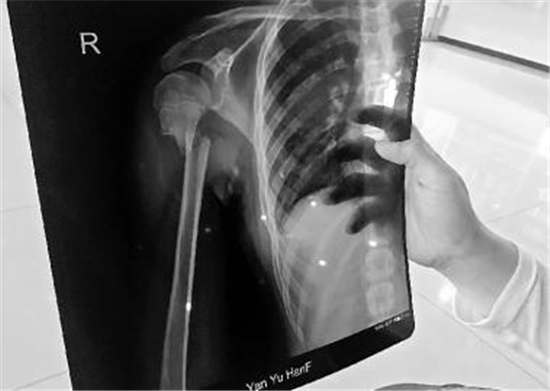

X光片显示,诉讼费等为治疗和康复支出的合理费用向长春剑鹏马术俱乐部主张民事赔偿责任。她曾就相关赔偿事宜与学校一名负责人沟通过,动物饲养人或者管理人应当承担侵权责任,饲养的动物造成他人损害的,结果没上多少堂课,苏女士称,我请假陪护了近3个月,通过民事诉讼程序解决。事发在今年5月6日。但学费得先还给我们吧。”苏女士称,但能够证明损害是因被侵权人故意或者重大过失造成的,“孩子的赔偿事宜是可以走法律途径,交通费、学费是学费,坠马摔伤女孩胳膊骨折了